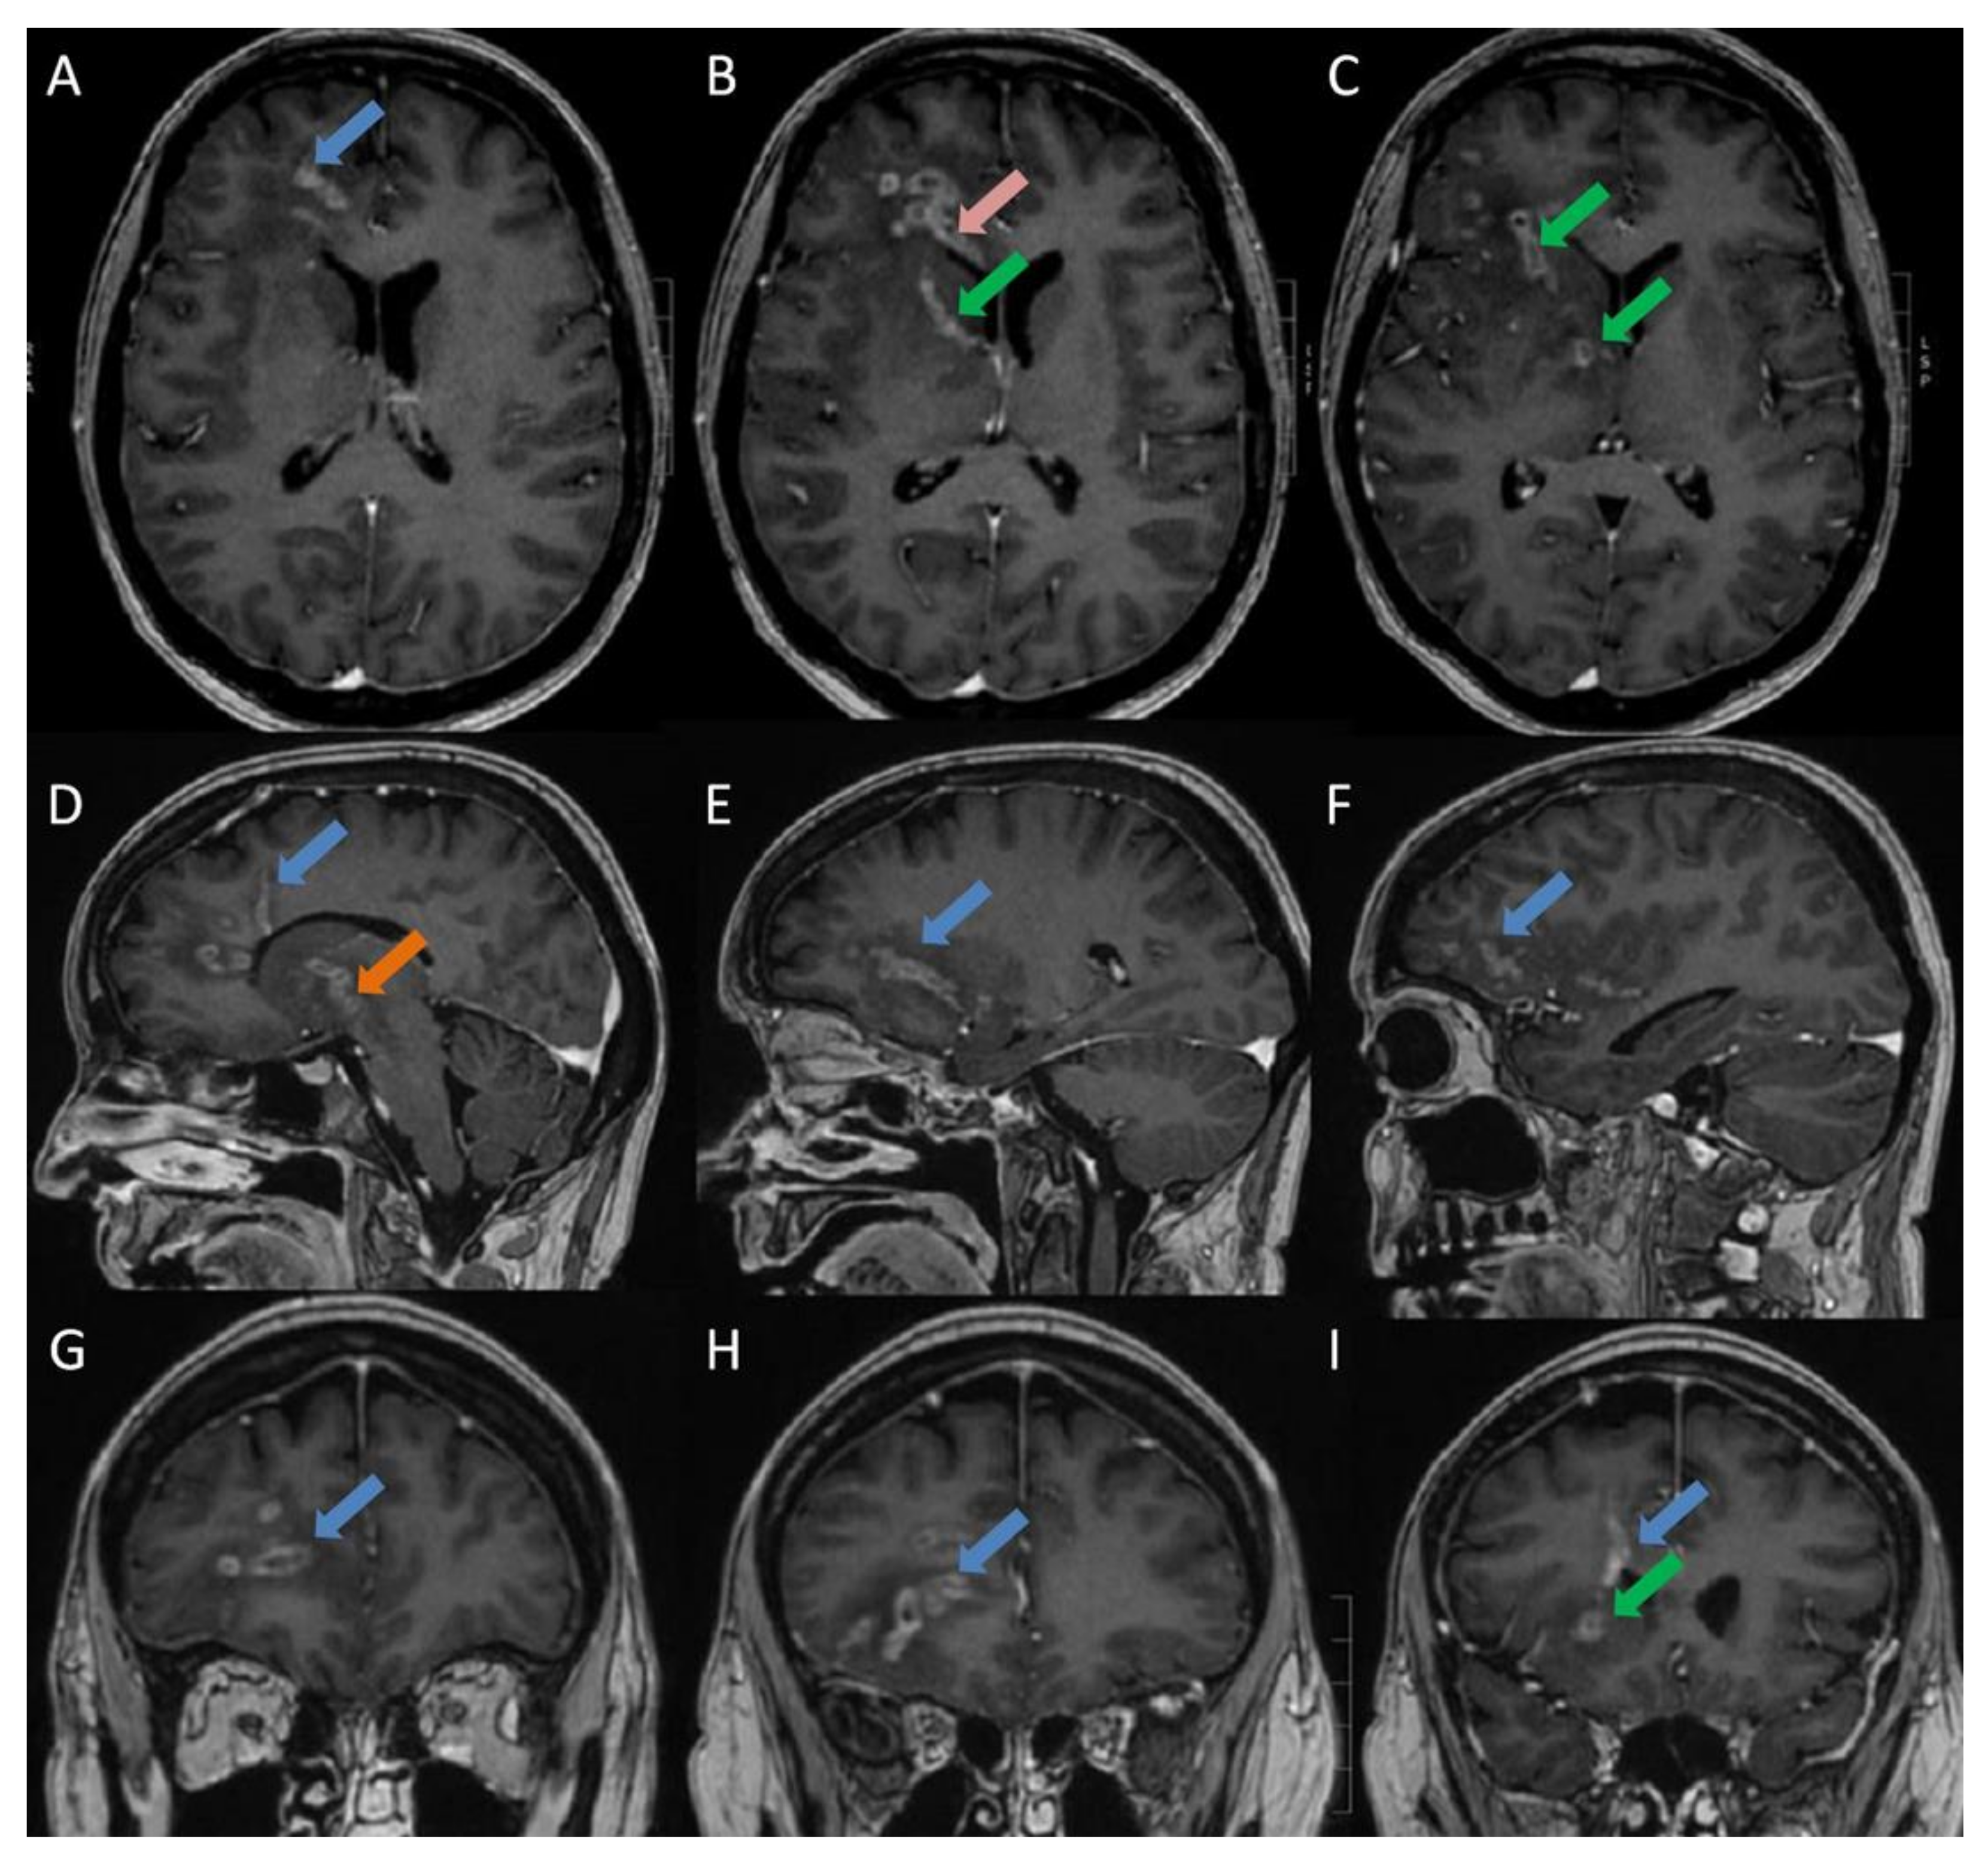

- Slezák, O.; Žižka, J.; Kvasnička, T.; Dvořáková, R.; Česák, T.; Ryšková, L.; Ryška, P.; Eliáš, P. Worm-like appearance of Listeria monocytogenes brain abscess: Pesentation of three cases. Neuroradiol. 2020, 62, 1189–1193. [Google Scholar] [CrossRef] [PubMed]